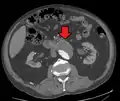

A ruptured AAA with an open arrow marking the aneurysm and the closed arrow marking the free blood in the abdomen

An axial contrast-enhanced CT scan demonstrating an abdominal aortic aneurysm of 4.8 by 3.8 cm